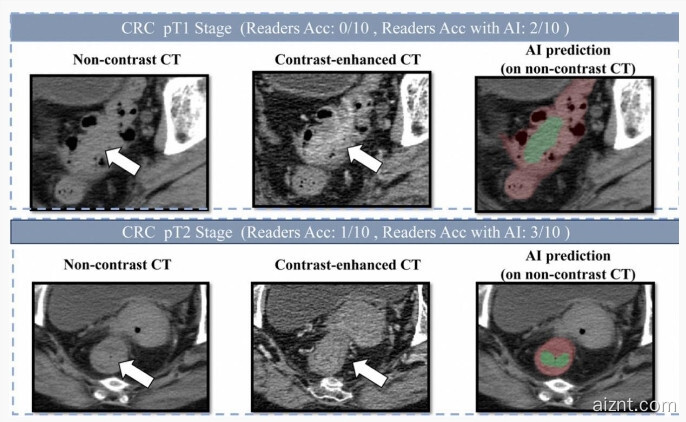

为了减轻肠道内容物对影像判读的影响,技术团队采用“先定位、后诊断”的深度学习架构,并重点针对小于 3 厘米的早期肿瘤进行训练。通过两阶段学习策略,模型可以更好地分割复杂的肠道区域,从而更准确地识别可疑病灶。